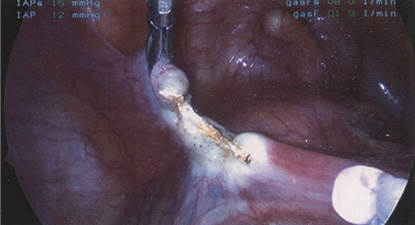

Если оставить в стороне эти достоинства и недостатки, то техника лапароскопической гистерэктомии фактически идентична технике лапаротомической гистерэктомии. В самом начале операции, если она выполняется лапароскопическим методом, необходимо осмотреть всё операционное поле, воспользовавшись для этого панорамным обзором (рис. 12-33—12-37). Операцию начинают с коагуляции и пересечения круглых связок, чем обеспечивается доступ к широкой связке (рис. 12-38—12-40). Брюшину, переходящую с купола мочевого пузыря на переднюю поверхность матки, вскрывают. Пузырь отсепаровывают от матки острым путём (рис. 12-41). После этого вскрывают задний листок широкой связки, а затем принимают решение, оставлять или удалять яичники. Если принято решение оставить яичники, то коагулируют и пересекают собственные связки яичников и маточные трубы (рис. 12-42). Если принято решение удалить яичники (то есть выполнить сальпингоофорэктомию), то с обеих сторон выполняют диссекцию мочеточников от воронко-тазовых связок, которые затем отсепаровывают, коагулируют и пересекают (рис. 12-43). Затем ткань широкой связки отделяют от маточных сосудов (отпрепаровывая их), изолировав, таким образом, мочеточники от маточных сосудов (рис. 12-44 А). Восходящие ветви маточных сосудов коагулируют справа и слева, а затем пересекают (рис. 12-44 Б, В).

Рис. 12-38. А. Круглая связка коагулирована и рассечена. Разрез продолжен на широкую связку. Б. Вскрыта правая широкая связка. В. Коагулирована правая круглая связка. Г. Справа рассечена складка брюшины мочевого пузыря. Д. Коагулированы и пересечены левая круглая связка, маточная труба и собственная связка яичника. Е. Увеличенное изображение Д.